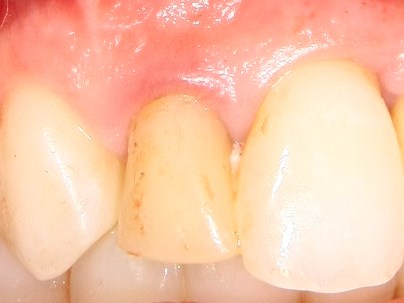

Немедленная имплантация — оптимальное решение в любой клинической ситуации